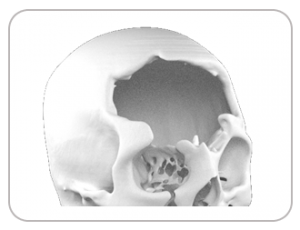

MR. Jatin had to loose large parts of his cranium due to severe Cranial Osteomyelitis. After successful treatment to control the infection, Medicad was approached to develop customized cranial plates for this complicated condition. Medicad team decided to go for a multi-material plate development approach to keep the cost down while maintaining aesthetics and to prevent infection relapse. PMMA with antibiotic was used as the material of choice to cover highly infected area while thin plate Titanium was used for the frontal and parietal regions so as to adjust for modification to defect edges during Cranioplasty.

DEFECT

DESIGNED IMPLANT

MANUFACTURED IMPLANT